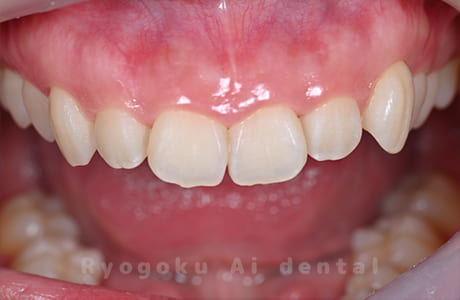

STEP 4

- 術後

- 手術後の状態の確認と記録を取ります。

笑った時に歯茎が見えてしまうガミースマイルを改善したいとのことでご来院された患者様です。術後も大変満足していただきました。